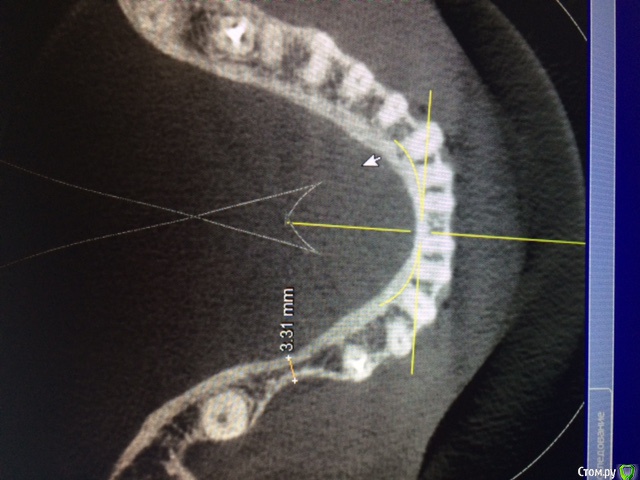

Аслан Опубликовано 24 января, 2015 Поделиться Опубликовано 24 января, 2015 Для начала лучше правильно заливать фотки. Не всем удобно вертеть монитор компа.Ситуация банальная. Их обсуждалось много уже. Нкр (апатос в перемешку с ауто, имплантация. Хотите - одномоментно, хотите раздельно. 1 Ссылка на комментарий